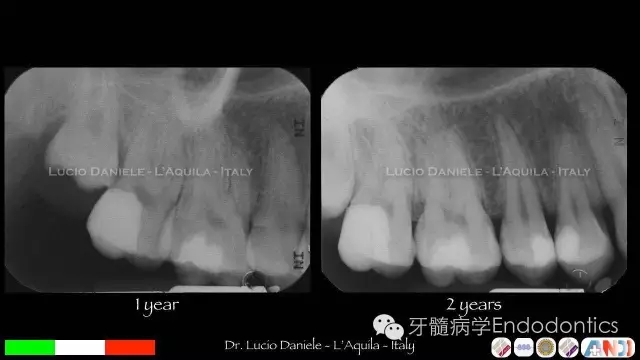

圖7.隨訪1年、2年

圖8.隨訪4年、11年